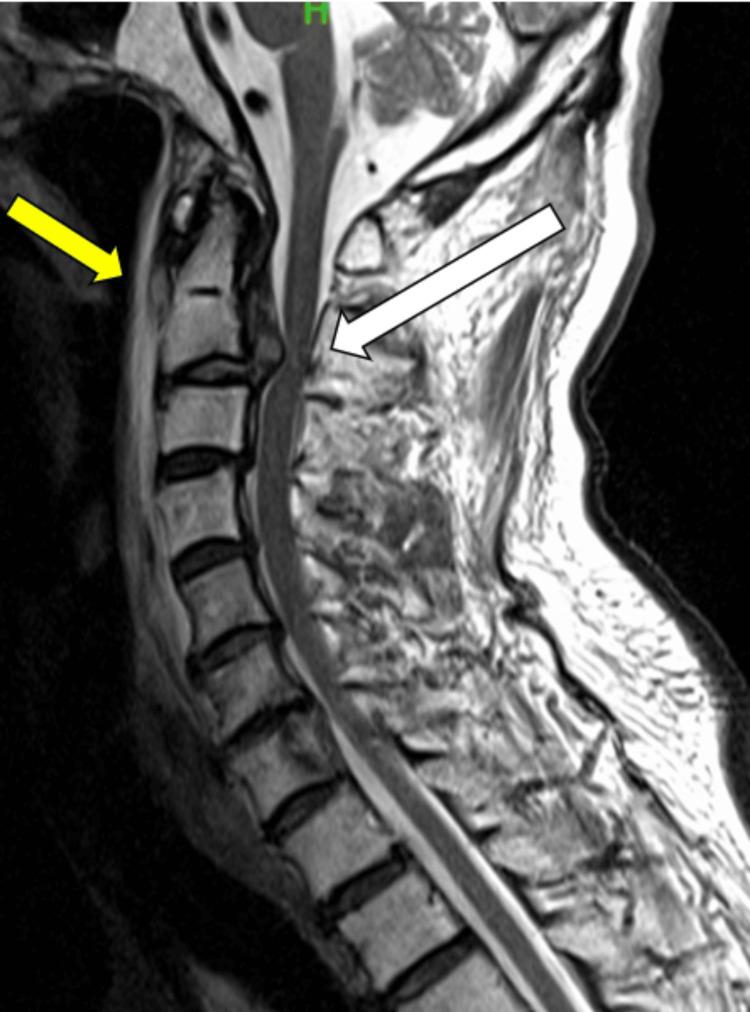

Traumatic herniations of the upper cervical spine are rare, with a higher likelihood of occurrence in older individuals. Their associated neurological symptoms can vary widely, often leading to delays in clinical diagnosis. We report the case of an 86-year-old man who developed neurological symptoms after a fall. Initially, intracranial pathology was suspected, and a head magnetic resonance imaging (MRI) revealed small chronic subdural hematomas, which were managed conservatively. However, as his paralysis progressed over the following days, a repeat brain CT showed no significant changes. Suspecting cervical spine involvement, further imaging identified a C2/3 disc herniation. The patient underwent emergency cervical laminoplasty, but postoperative subluxation required additional surgery, including C1-3 posterior fusion and C2/3 anterior fusion. Post-surgery, the patient exhibited improvement in paralysis affecting both the upper and lower extremities and a reduction in sensory deficits. Early diagnosis and treatment are crucial to improve neuropathic outcomes. A thorough understanding of the symptoms and characteristics of neurological damage to the upper cervical spine can significantly contribute to favorable results. Clinicians should be well-acquainted with this pathological condition.